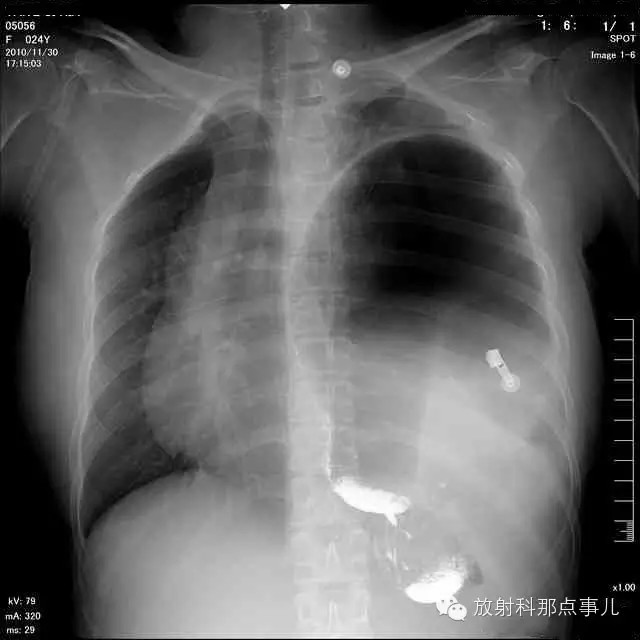

门诊腹部透视发现左侧胸腔巨大气液平面,为排除膈疝口服钡剂,但造影剂未见进入胃内。嘱住院,外科给予胃肠减压、补液等处理常规处理(未引流出明显气、液体)。5个半小时后再次检查,见少量造影剂进入消化道;为进一步了解情况,予泛影葡胺分别经胃管推注及口服,但均未进入胃内。当天进行外科急诊手术。

更正:检查时间在左上方。

大部分胃、脾及横结肠均经过胸肋三角疝入左侧胸腔内,并见疝环形成。

考虑该患者因生产过程中腹压急剧升高,导致腹内脏器经膈肌缺损或薄弱部位进入胸腔内。